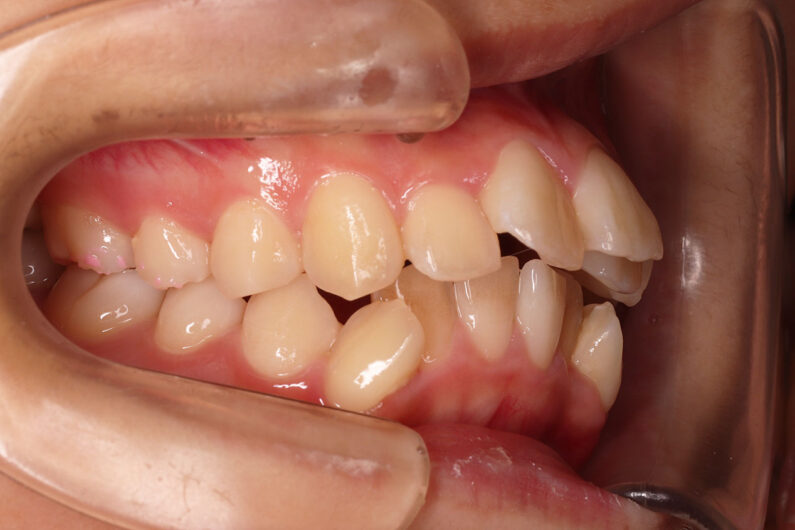

他院から紹介の患者さんです。 前歯、下の歯のガタツキをきれいにしたいということで治療を決断されました。

上顎前歯6mm、下顎前歯2.5mmの前突の状態で、口唇も前突しています。 小臼歯抜歯したスペースを使い、叢生(がたつき)と前突した前歯の後退を目標にしました。 この方も希望により、アンカースクリューは使用せず、通常の顎間ゴムで対処してもらいました。